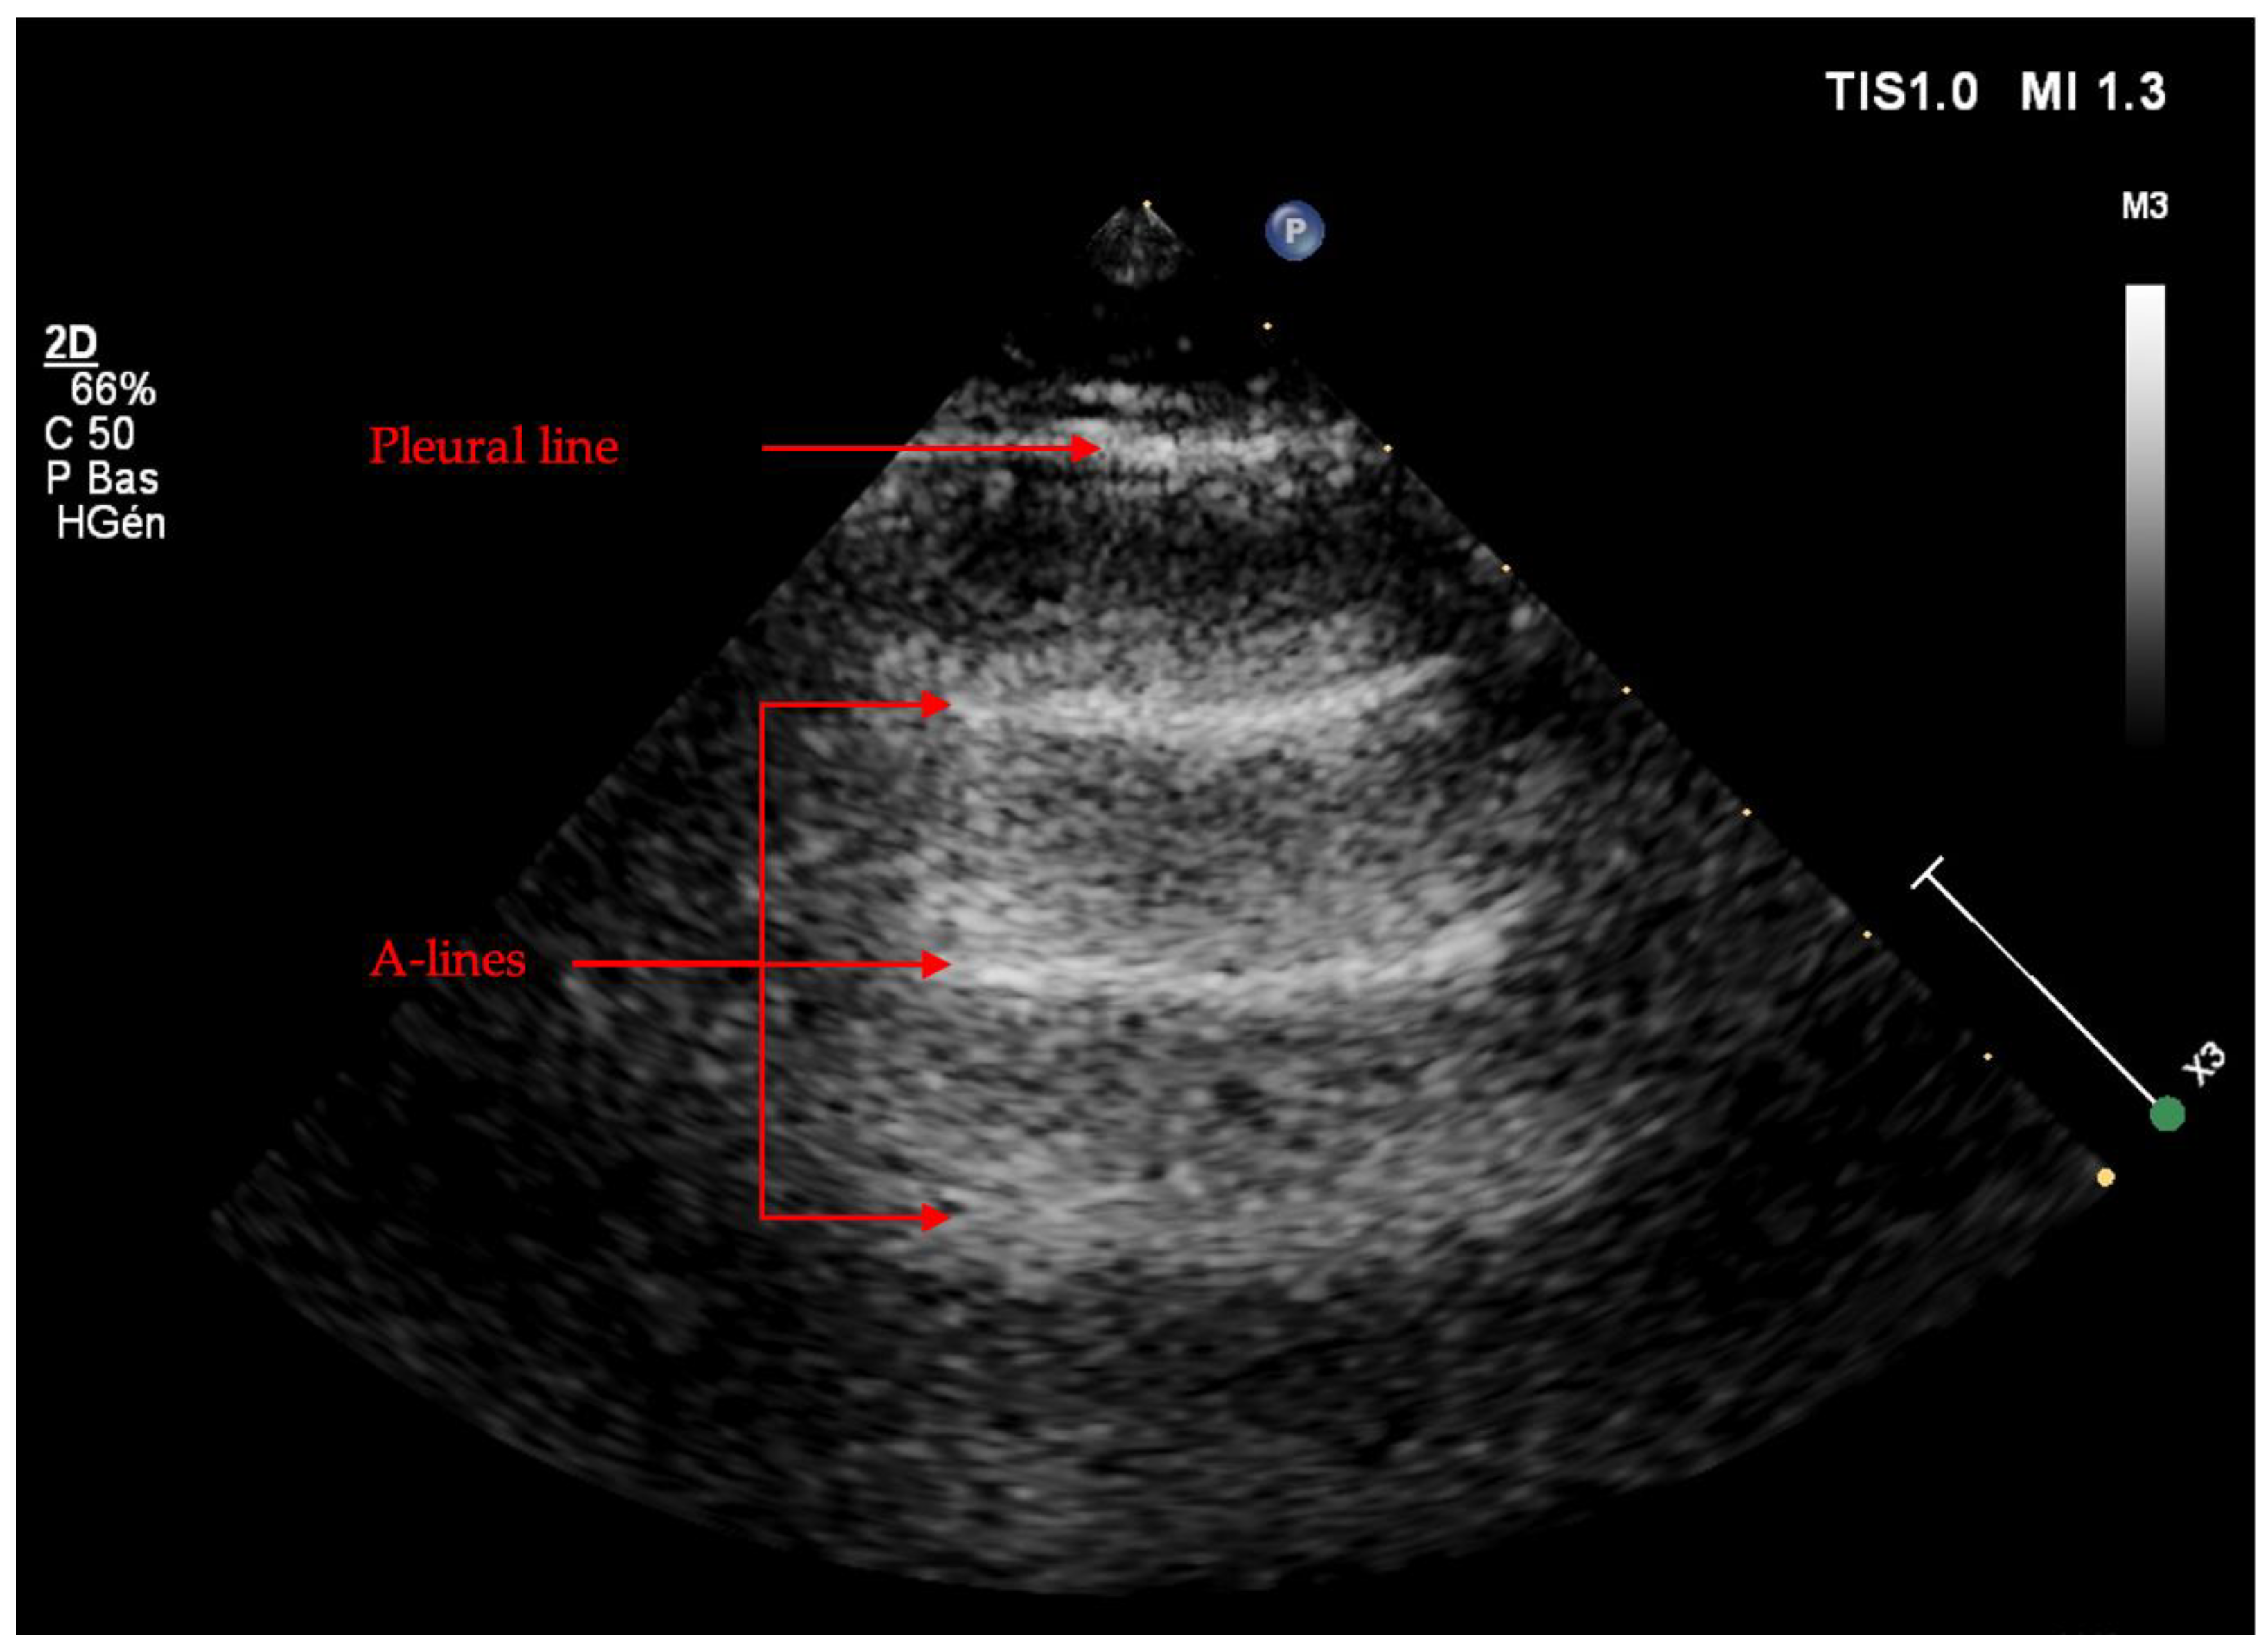

Artifacts

Pneumothorax